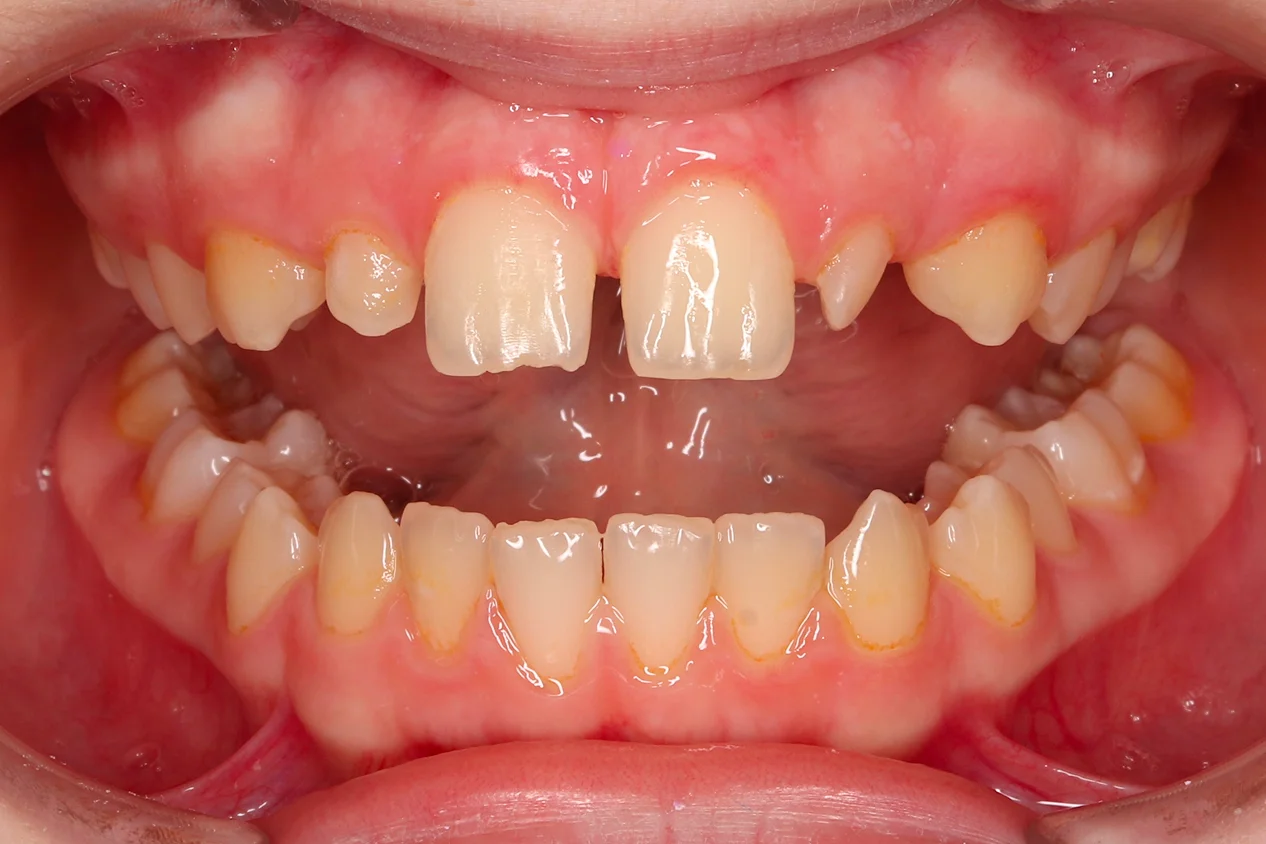

Аномалии формы: от шиловидного резца до секторальной одонтоклазии.

Микродентия, макродентия, синодонтия, геминация — диагностика и тактика лечения. Сочетанные случаи. Показания к подростковому протезированию при микродентии.

Пороки твёрдых тканей: дифференциальная диагностика

Молярно-резцовая гипоминерализация (MIH), флюороз, несовершенный амелогенез, дисплазии дентина — клинические признаки каждого состояния и границы между ними. Классификация Wuerzburg 2.0. Дисплазии дентина: от облитерации пульповой камеры до «зубов-призраков».